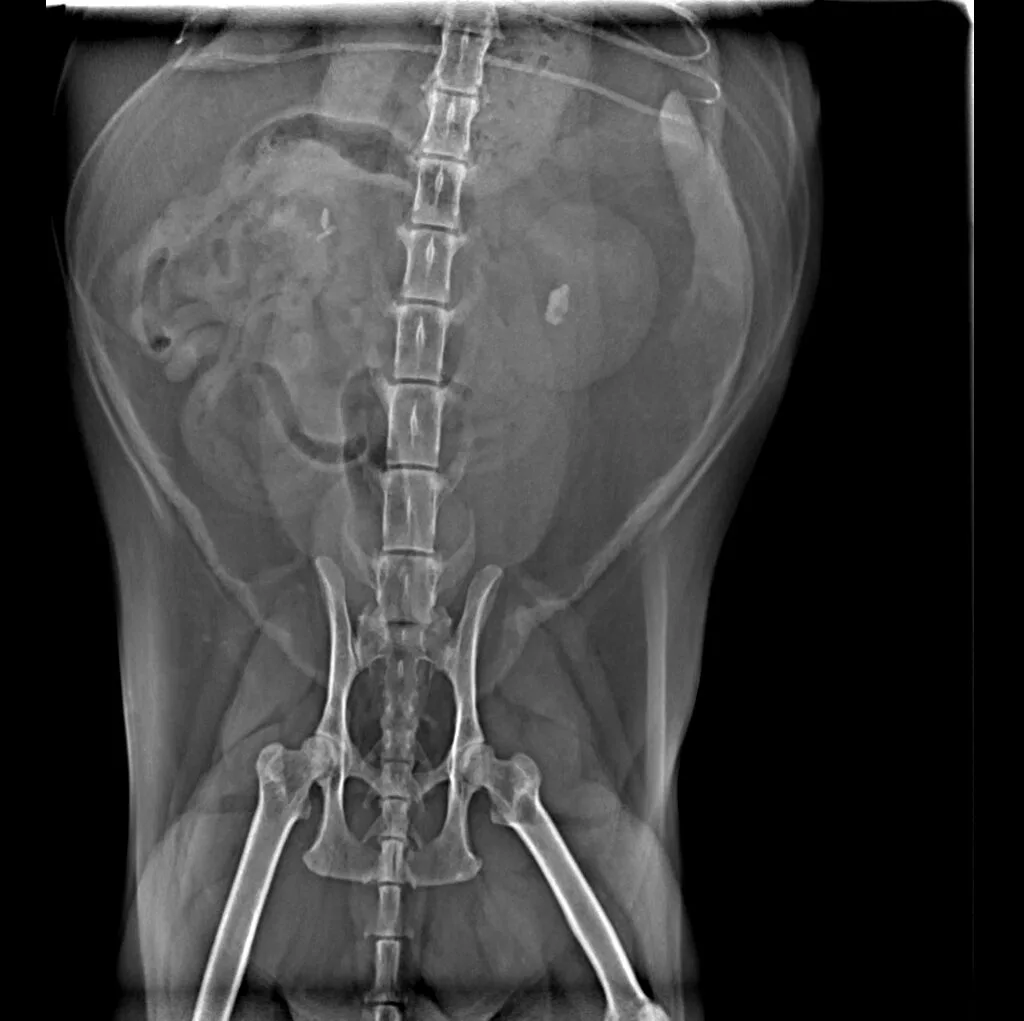

🔹 Abdominal & Gastrointestinal Issues – Detecting obstructions, tumors, or organ abnormalities

🔹 Cancer Screening – Locating tumors and assessing disease progression